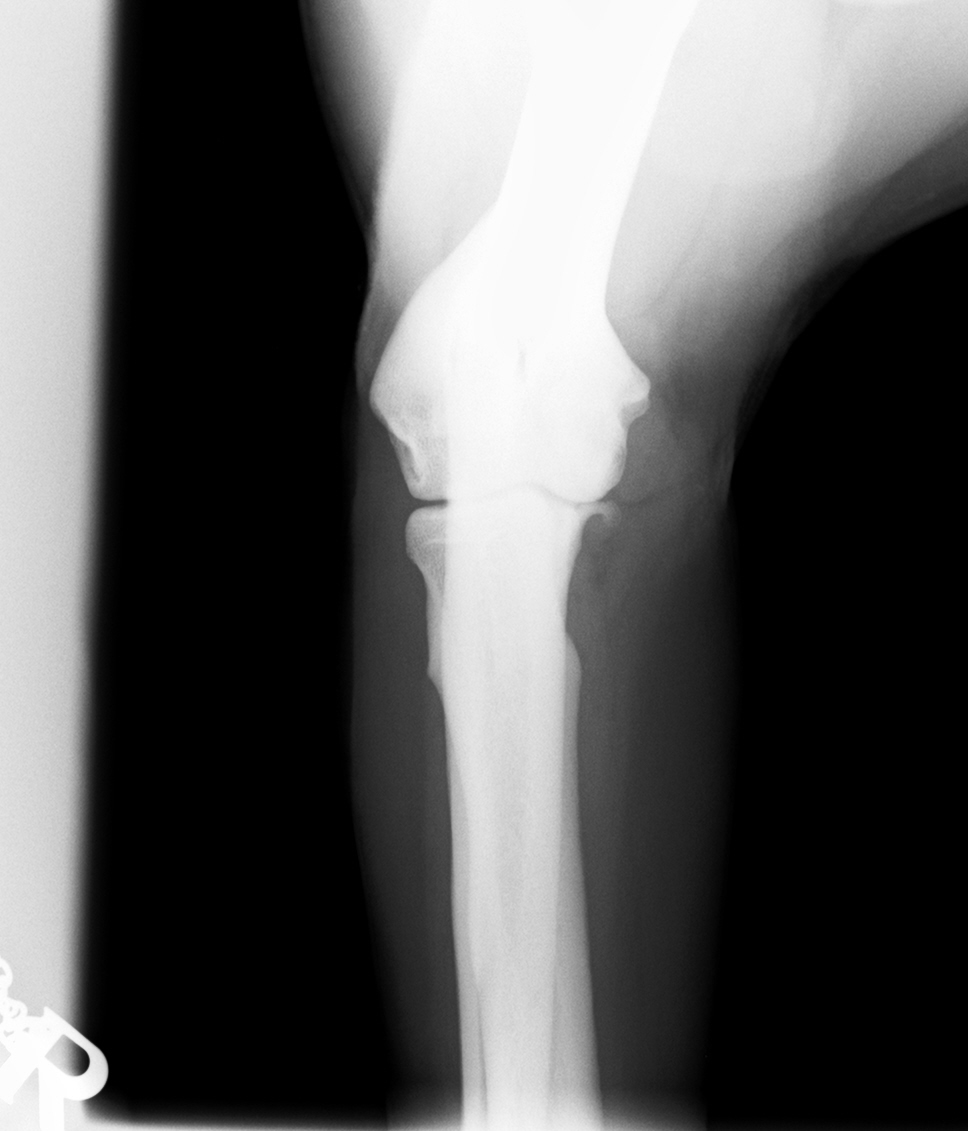

Im August 2013 wurde ein acht Jahre alter männlich kastrierter Labrador mit beidseitig hochgradiger  Ellenbogengelenksarthrose vorgestellt. Der Hund war beidseits wegen eines frakturierten Processus Coronoideus (Der Proccesus Coronoideus stellt einen wichtigen knöchernen Stabilisator des Ellenbogengelenks dar) operiert, einseitig nachoperiert und auf beiden Seiten mehrfach mit Cortison-Injektionen behandelt worden.

Schon drei Wochen nach der Therapie besserte sich das Gangbild deutlich, der Hund lahmte nach Aussagen der Besitzer viel weniger und wollte wieder länger spazieren gehen. Zeitweise konnte sogar die Dosis entzündungshemmender Medikamente um die Häfte reduziert werden.

Insgesamt haben wir über 40 Hunde mit C-Pet behandelt, darunter war nur ein Therapieversager, bei allen anderen kam es nach Aussage der Besitzer zu einer deutlichen Verbesserung der Lahmheit. Dabei wurde von uns im überwiegenden Teil der Fälle Ellbogengelenke behandelt, dreimal ein Kniegelenk, einmal eine Hüftgelenk und einmal Zehengelenke.